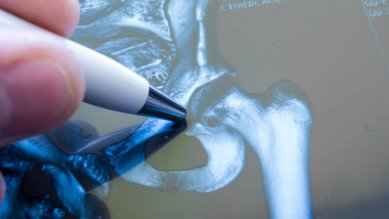

Kalça eklemi yanı kırığı

Yaşlı insanlar düştüklerinde sıklıkla kalça yakınındaki bir kemikleri kırılır (örneğin femur boynu kırılması). Böyle bir kırık genellikle ameliyat gerektirir.